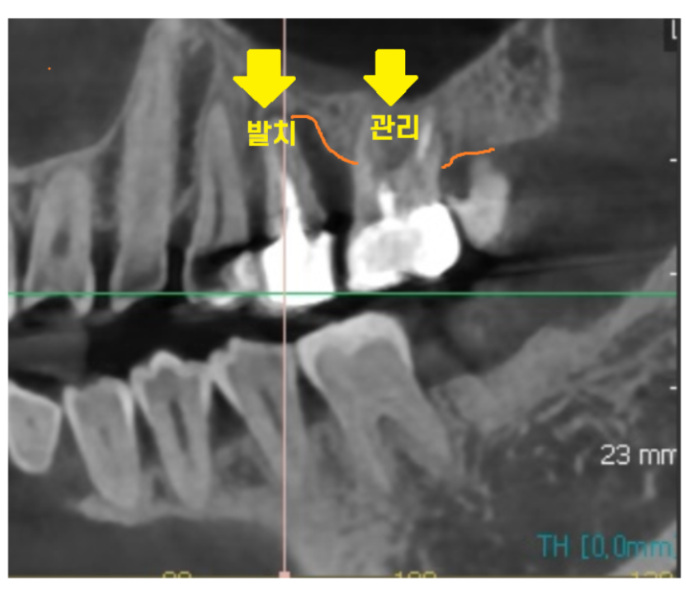

221214

발치 여부, 즉시 식립 가능성 판단

발치 후 뼈이식만 먼저 진행할 것인지

발치와 동시에 수술이 진행할 수 있을지 여부가 말이죠.